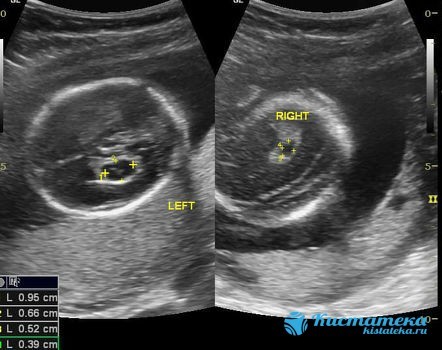

- Кисты сосудистых сплетений. Возникают еще в период внутриутробного развития. Чаще всего данные полостные образования регистрируются уже на 28 неделе беременности. После рождения могут остаться на всю жизнь. Обычно у ребенка нет никаких неблагоприятных симптомов, все протекает без каких-либо клинических изменений.

Сосудистые сплетения у плода образуются на сроке 18-19 недель. Именно в этот период, при проведении УЗИ могут быть обнаружены первые признаки кист, которые выглядят, как эхонегативные образования. Чаще всего в срок от 20 до 24 недель, когда идет активное формирование головного мозга, размер кисты уменьшается, и она полностью исчезает.

Статистика утверждает, что кисты сосудистого сплетения образуются в 1-2% случаев. Самопроизвольное их рассасывание происходит к 24-й неделе в 90% случаев. Размер их считается мелким до 5 мм.

Практически нет. Киста правого сосудистого сплетения так же мало опасна, как и образование слева. В половине всех случаев диагностики кисты оказывались двусторонними. Особенно это касается образований, обнаруженных у плода.

Киста сосудистого сплетения у плода до 20 недель представляет собой округлую полость, заполненную прозрачной жидкостью. При проведении скрининга капсулу обнаруживают не позднее 2 триместра. К этому периоду она обычно полностью рассасывается, когда происходит стабилизация формирования нервной системы.

Правосторонняя патология отличается от левосторонней только расположением. Многочисленные наблюдения говорят о том, что нормализация сосудистого сплетения происходит в период до 22-24 недель беременности. Киста в правом сосудистом сплетении, имеющая нормальные размеры, не оказывает негативного влияния на нервную ткань.